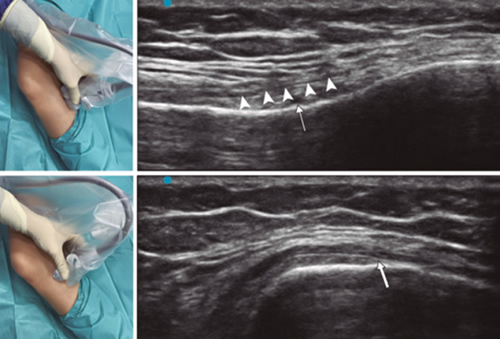

Figura 1